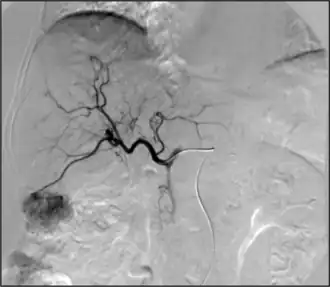

La quimioembolización es un procedimiento de radiología intervencionista realizado en la sala de angiografía. El procedimiento se realiza bajo anestesia local y según la técnica de Seldinger a través de una arteria periférica. Habitualmente se utiliza como acceso la arteria femoral común aunque puede accederse a través de las arterias axilar, humeral o radial Previamente a la quimioembolización debe realizarse una angiografía del tronco celiaco, de la arteria mesentérica superior y de la arteria hepática común con el objetivo de valorar las posibles variantes anatómicas, confirmar la permeabilidad portal y estudiar la localización y la vascularización de las lesiones tumorales hepáticas. A continuación se introduce un microcatéter de forma selectiva a las arterias nutrícias de la lesión tumoral. Esto se hace para maximizar la cantidad de la dosis de quimioterapia que se dirige al tumor y minimizar la cantidad del agente quimioterapéutico que podrían dañar el tejido hepático normal.